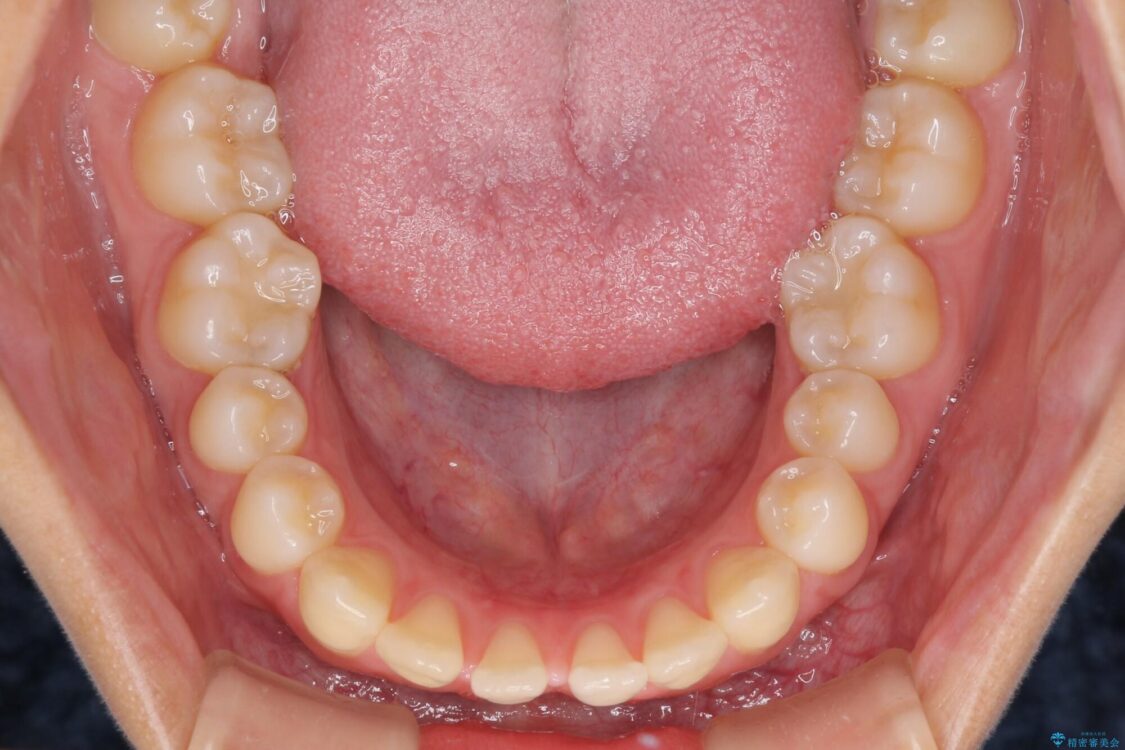

前歯の上下スペースと前歯の隙間を気にして来院された患者様です。

飲み込みや話をするときに舌を突出させる癖が強くあり、それが原因でスペースが空いていました。

舌癖を改善するためのトレーニングを行いながら、インビザラインにより上下の前歯の隙間を閉じていくこととしました。

治療前

• 隙間だらけの歯列 インビザラインで改善 治療前画像